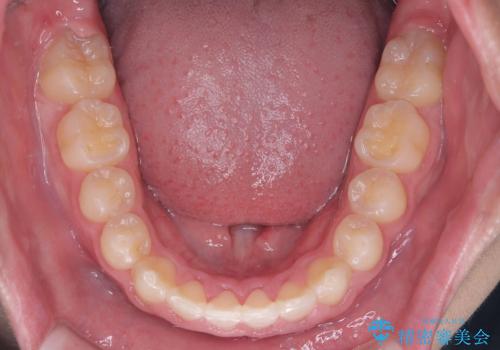

八重歯・歯並びのデコボコとディープバイトを改善した抜歯ワイヤー矯正症例

八重歯などの歯列のデコボコが綺麗に改善され、患者様にも大変喜んでいただけました。また、咬み合わせが深い「ディープバイト」も併せて改善し、見た目だけでなく機能面でもバランスの取れた咬合を獲得しています。